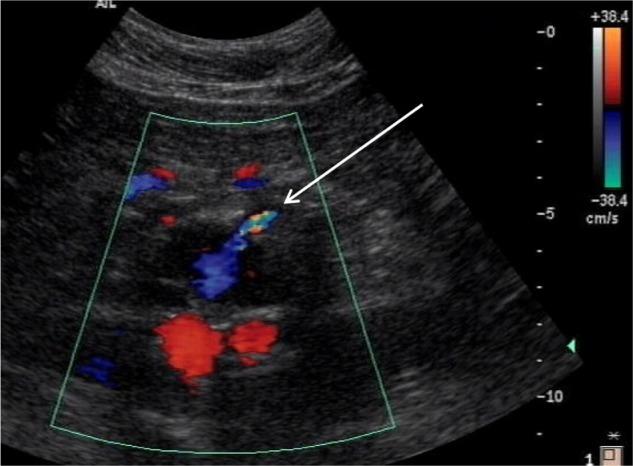

Type II endoleaks are the most common endovascular complications of endovascular abdominal aortic aneurysm repair (EVAR); however, there has been a divided opinion regarding their significance in EVAR. Some advocate a conservative approach unless there is clear evidence of sac expansion, while others maintain early intervention is best to prevent adverse late outcomes such as rupture. There is a lack of level-one evidence in this challenging group of patients, and due to a low event rate of complications, large numbers of patients would be required in well-designed trials to fully understand the natural history of type II endoleak. This review will discuss the imaging, management, and outcome of patients with isolated type II endoleaks following infra-renal EVAR.

II型内漏是腹主动脉瘤腔内修复术(EVAR)最常见的血管内并发症;然而,对于其在EVAR中的重要性存在不同观点。一些人主张采取保守方法,除非有明确的瘤体扩张证据,而另一些人则认为早期干预最有利于预防诸如破裂等不良晚期结局。在这类具有挑战性的患者群体中缺乏一级证据,并且由于并发症发生率较低,需要大量患者参与精心设计的试验才能全面了解II型内漏的自然病程。本综述将讨论肾下EVAR术后孤立性II型内漏患者的影像学表现、治疗及预后。